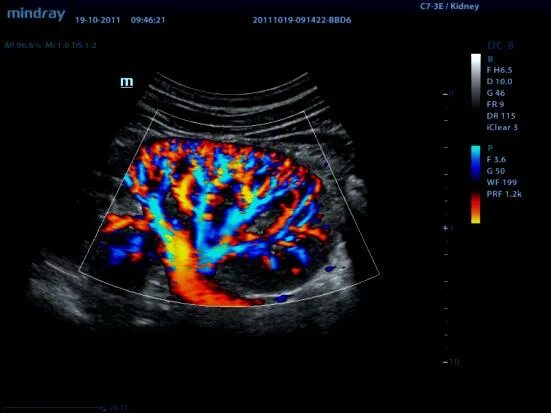

Что такое при цдк